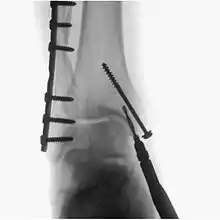

Fluoroscopy is used in various types of surgical procedure, such as orthopaedic surgery and podiatric surgery. In both of those, it is used to guide fracture reduction and in use in certain procedures that have extensive hardware.[5]